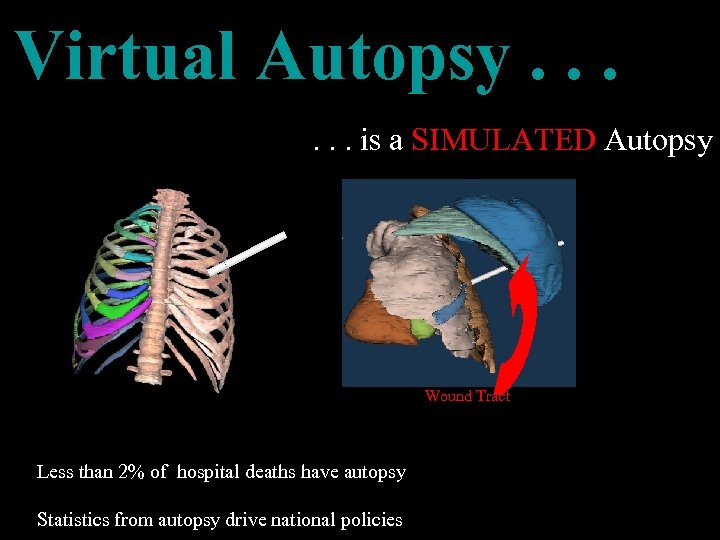

Virtual Autopsy. . . is a SIMULATED Autopsy Wound Tract Less than 2% of hospital deaths have autopsy Statistics from autopsy drive national policies

Virtual Autopsy. . . is a SIMULATED Autopsy Wound Tract Less than 2% of hospital deaths have autopsy Statistics from autopsy drive national policies